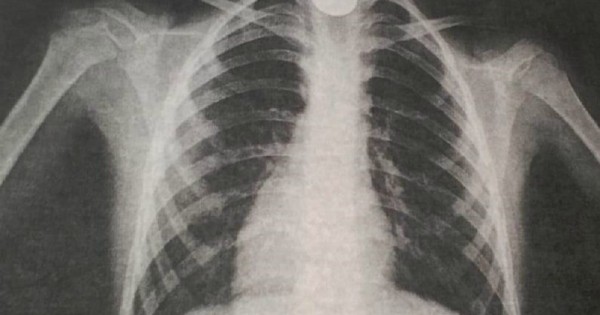

Belgili bolǵandaı, oınap otyrǵan 9 jastaǵy bala baıqamaı tıyndy jutyp qoıǵan. Bir saǵattan soń onyń tynys alýy qıyndap, jaǵdaıy nasharlaǵan. Budan soń, ol oblystyq kópbeıindi balalar aýrýhanasyna jetkizilgen. О́kpe jasýshalaryn túsirgen rentgenografııa qorytyndysy óńeshtiń joǵarǵy jaǵynda bógde zattyń turǵandyǵyn anyqtaǵan.